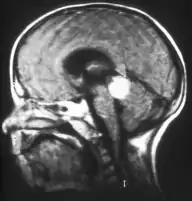

MRI pattern of retinoblastoma with optic nerve involvement (sagittal enhanced T1-weighted sequence)

If the eye examination is abnormal, further testing may include imaging studies, such as computerized tomography (CT), magnetic resonance imaging (MRI), and ultrasound.[28] CT and MRI can help define the structure abnormalities and reveal any calcium depositions. Ultrasound can help define the height and thickness of the tumor. Bone marrow examination or lumbar puncture may also be done to determine any metastases to bones or the brain.

Traditional ultrasound B scan can detect calcifications in the tumour while high-frequency ultrasound B scan is able to provide higher resolution than the traditional ultrasound and determine the proximity of the tumour with front portion of the eye. MRI scan can detect high-risk features such as optic nerve invasion; choroidal invasion, scleral invasion, and intracranial invasion. CT scan is generally avoided because radiation can stimulate the formation of more eye tumours in those with RB1 genetic mutation.[35]